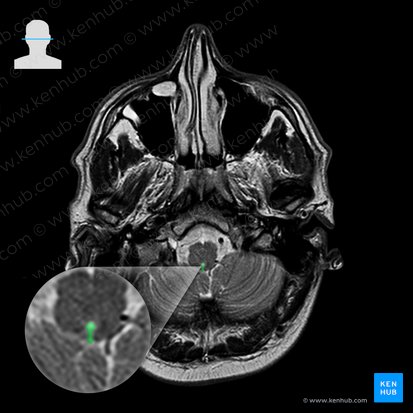

El tronco encefálico (tronco del encéfalo, tronco cerebral, tallo del encéfalo o tallo encefálico) es la parte más caudal del encéfalo y está conformada por el mesencéfalo, el puente y el bulbo raquídeo (médula oblongada). Cada uno posee su propia estructura y función. Entre los tres regulan la respiración, el ritmo cardíaco, la presión sanguínea, entre otras funciones importantes. Todas estas funciones son posibles gracias a que alberga los núcleos de los pares craneales y además da paso a numerosas vías importantes del sistema nervioso central.

El tronco encefálico comienza a nivel de los pedúnculos cerebrales adelante y a nivel de la lámina tectal o cuadrigémina por detrás. Continúa caudalmente siguiendo una dirección ligeramente posteroinferior hasta que termina a nivel de la decusación de las pirámides (a nivel del foramen magno del cráneo).

El tronco encefálico es más ancho arriba y más estrecho abajo. Podemos distinguir en él tres partes principales:

Mesencéfalo

El mesencéfalo es el segmento más corto del tronco encefálico. Se extiende caudalmente desde la base del tálamo hasta el surco pontopeduncular. Pasa a través de una abertura ubicada en el tentorio del cerebelo (una extensión de la duramadre). El origen embrionario de esta estructura es una de las tres vesículas primarias del tubo neural, también llamada mesencéfalo, ubicada sobre el cuarto par de somitos. Esta vesícula está ubicada entre el prosencéfalo y el rombencéfalo.

Configuración externa

El límite superior del mesencéfalo es una línea imaginaria horizontal que se extiende desde la comisura posterior (bajo la glándula pineal y sobre los colículos superiores) hasta los cuerpos mamilares. Por debajo, el mesencéfalo termina en el surco pontopeduncular anteriormente y en el velo medular superior posteriormente. El surco pontopeduncular es un surco horizontal poco profundo ubicado entre el borde superior del puente y los pedúnculos cerebrales. El velo medular superior es una delgada capa de tejido nervioso que forma el techo del cuarto ventrículo.

Externamente y por su cara anterior, el mesencéfalo se caracteriza por la presencia de dos tallos conocidos como los pedúnculos cerebrales. Estos representan los numerosos tractos ascendentes y descendentes que comunican la corteza cerebral con el puente y la médula espinal. Existe una depresión poco profunda entre los pedúnculos conocida como fosa interpeduncular. La sustancia perforada posterior (a través de la cual pasan vasos sanguíneos hacia y desde el mesencéfalo) forma el piso de la fosa. En esta fosa se encuentran el nervio oculomotor, la bifurcación de la arteria basilar en sus ramas terminales (las arterias cerebrales posteriores) y los cuerpos mamilares del hipotálamo. Los pedúnculos convergen caudalmente para encontrarse con el puente.

Los tractos ópticos discurren alrededor de cada lado del mesencéfalo para terminar eventualmente en el cuerpo geniculado lateral, el cual se encuentra posterior y lateralmente al tálamo. El cuerpo geniculado medial y el uncus del lóbulo temporal del cerebro también se ubican hacia lateral del mesencéfalo. La cara posterior del mesencéfalo posee dos pares de eminencias redondeadas que se conocen en conjunto como lámina tectal o lámina cuadrigémina. Este complejo consta de dos colículos superiores y dos inferiores, los cuales contienen sus núcleos respectivos. Cada colículo está separado de su homónimo contralateral mediante el frenillo del velo medular superior.

Las secciones transversales del mesencéfalo revelan más información acerca de la estructura y organización de esta parte del encéfalo. Este segmento del tronco encefálico está dividido en una lámina tectal (tectum = techo en latín), un tegmento (tegmentum = cubierta en latín) y los pedúnculos cerebrales.

La lámina tectal es la parte del mesencéfalo ubicada dorsal al acueducto cerebral (acueducto de Silvio), un conducto que conecta el tercer y el cuarto ventrículo. El tegmento por otra parte, es ventral al acueducto cerebral. Los pedúnculos cerebrales están constituidos por un conjunto de tractos ascendentes y descendentes que viajan desde y hacia el cerebro. Cada pedúnculo está separado del tegmento por la sustancia negra, que es una lámina pigmentada constituida por neuronas dopaminérgicas y gabaérgicas, las cuales producen el neurotransmisor que indica su nombre. Es importante considerar que si bien cada pedúnculo está separado del contralateral, estos son continuos entre sí en la línea media.